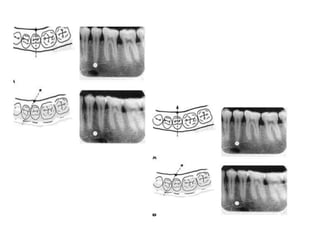

Four film survey:

Eight film survey:

Radiographic examinations

Four film

survey:

series consists of

a maxillary and

mandibular

occlusal

radiographs and

two posterior

bitewing

radiographs.

• This survey includes a

maxillary and

mandibular anterior

occlusal radiographs.

• Four molar periapical

• Two posterior

bitewings